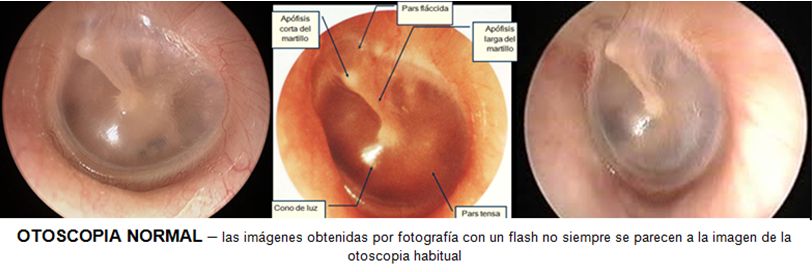

DIAGNOSTICO Y MANEJO DE LA OTITIS MEDIA AGUDA.